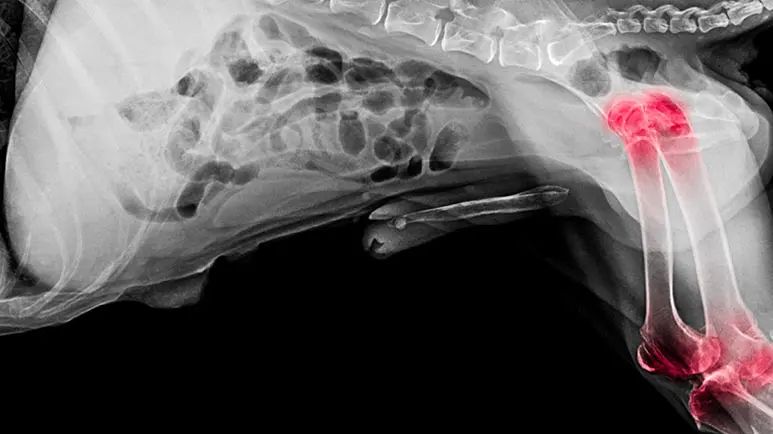

Since the vast majority of canine companions will at some point suffer from arthritis pain, it's important to keep abreast of what types of alternative therapies are available to help your dog remain comfortable and mobile. One of the most promising is laser therapy.

Laser Therapy Is Proving To Be a Miracle Treatment for Many Dogs With Arthritis